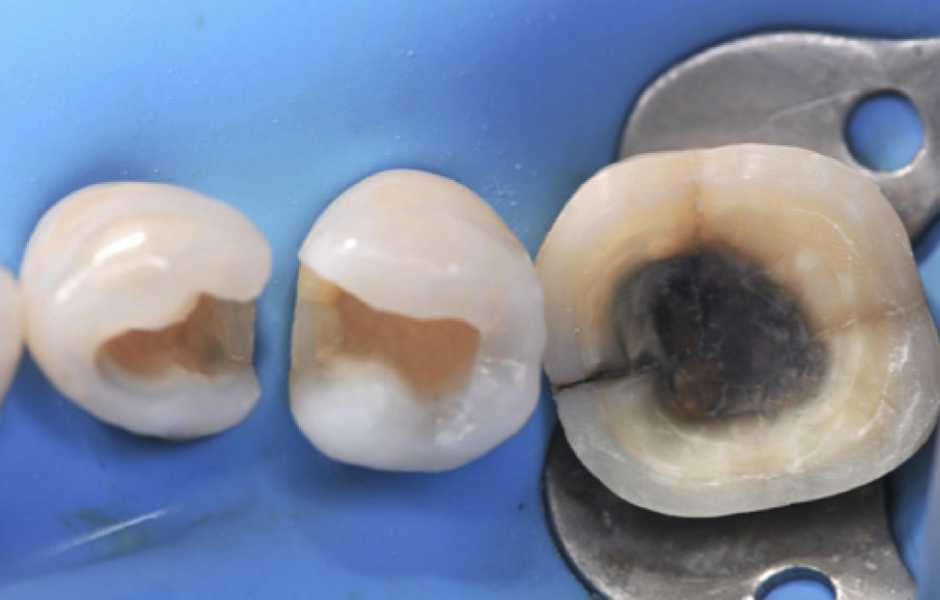

Obr. 2: Nasazení kofferdamu. Po nasazení kofferdamu byly staré výplně odstraněny a objevil se skutečný rozsah ztráty tvrdých zubních tkání.